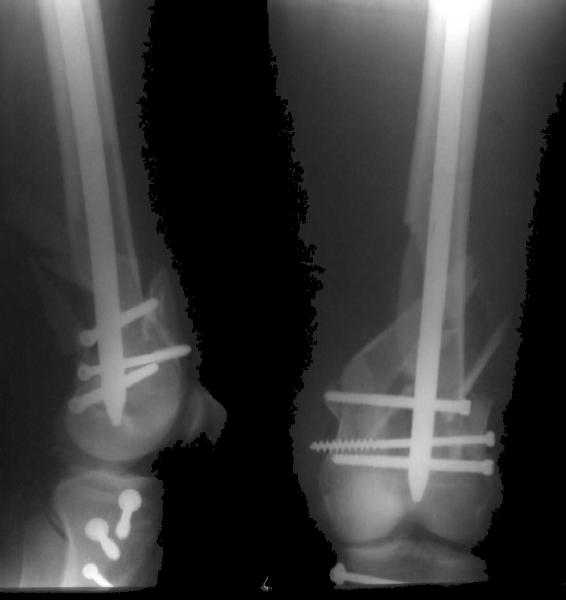

This is what we have done... As generally true for LISS look at the bone not the hardware.

There are two more srews above. The one not completely in got damaged head.

Zsolt